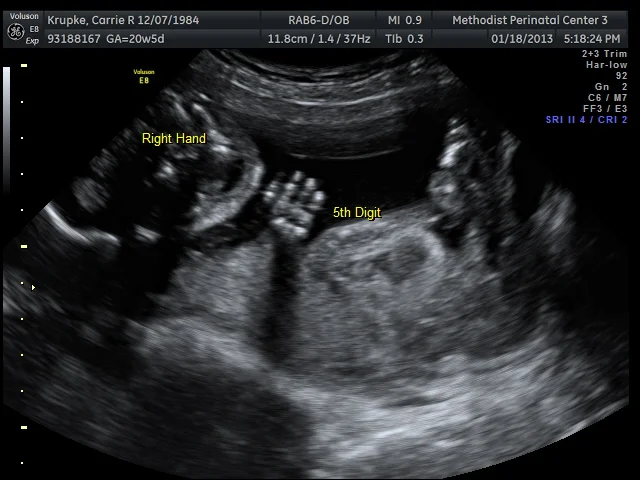

The full-time tech came in shortly afterwards and also commented how beautiful Baby’s heart was. She proceeded to go for shots of the spine and other appendages. Intermittently, she’d go looking to see if Baby was a He or She. Baby’s flip turn form was stellar the entire time, with its legs closed and feet above the head. (In true “Gerard flexibility” fashion as well.) So the tech would go from searching to measuring another body part. Rinse-repeat. Rinse-repeat.

At several points in that 75 minutes, I’d look at the tech and try to read her face. She was so focused, she’d look concerned, especially when she was looking at the spine. I asked her a few times if everything was ok and she’d smile and say, “Yup, this is my focus face. This Peanut is moving around so much, I have to be quick to click for the photo. Spine looks fantastic!” I’ll admit, this kinda looks like an underwater sea-creature.